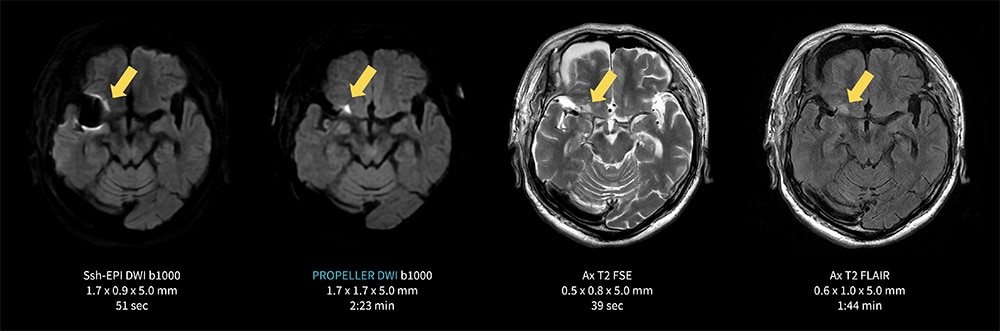

Case4 PROPELLER DWI/右中大脳動脈クリッピング後 陳旧性脳梗塞フォロー

70代、男性。右中大脳動脈のクリッピング術後フォロー。陳旧性の脳梗塞あり。

クリップ周囲の病変はシングルショットEPI DWIでは磁化率アーチファクトのため評価が難しいが、ROPELLER DWIによって磁化率アーチファクトの影響を最小限に抑えつつ梗塞部位(→)の可視化が可能となった一例。

図4 PROPELLER DWIによる 右中大脳動脈クリッピング後 陳旧性脳梗塞フォロー